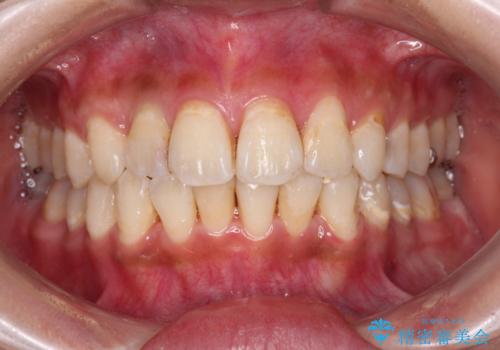

デコボコで磨きにくい前歯をスッキリと インビザライン矯正

- 虫歯が多く、磨きにくい歯並びを改善したいとのことで来院された患者様です。

歯列は叢生が認められる程度でしたが、やや前突感があったので、少しでも口が閉じやすくなるように仕上げる方針としました。

神経を取り除かれている歯3本以外にも虫歯が認められたため、事前に処置を行い、インビザラインにて矯正治療を行うこととしました。

歯磨きしやすくなるとともに、飛び出していた前歯も引っ込めて整えることができました。